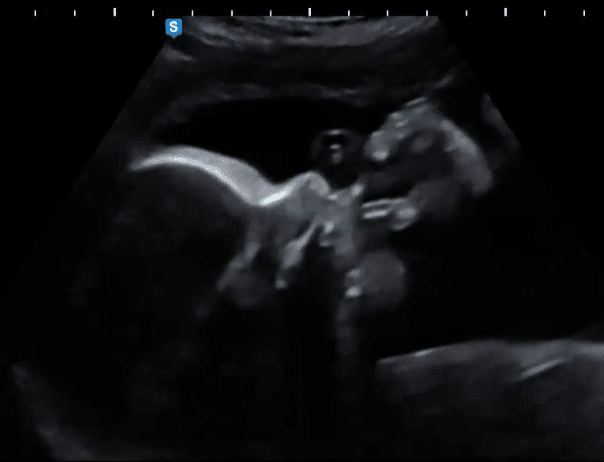

L’action de téter est un mouvement complexe, qui va impliquer jusqu’à 40 muscles différents ! Le bébé va s’y entrainer très tôt, avant la naissance, avec le liquide amniotique qu’il boit en grandes quantités. Mais ce qui va changer après la naissance c’est l’arrivée de la respiration !

Les 1ers signes de succion sont visibles en échographie dès la 10ème semaine